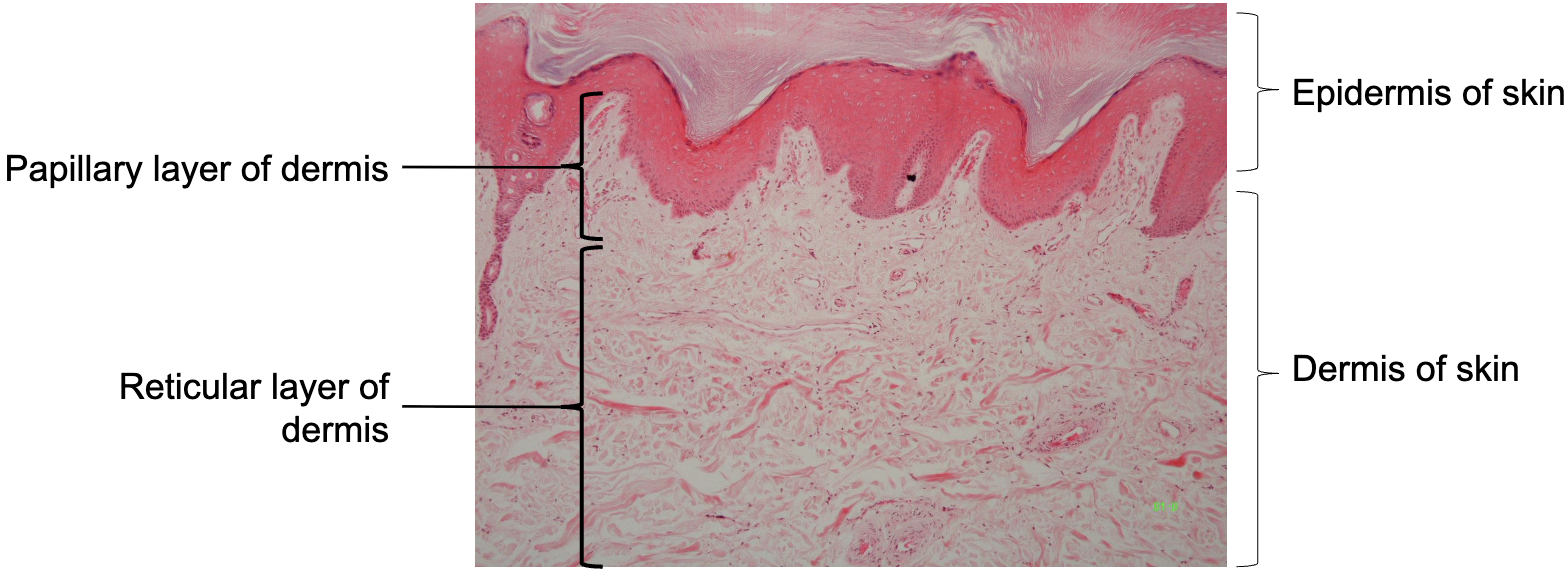

5

New cards

Label strata of epidermis

Thin skin: Strata of epidermis